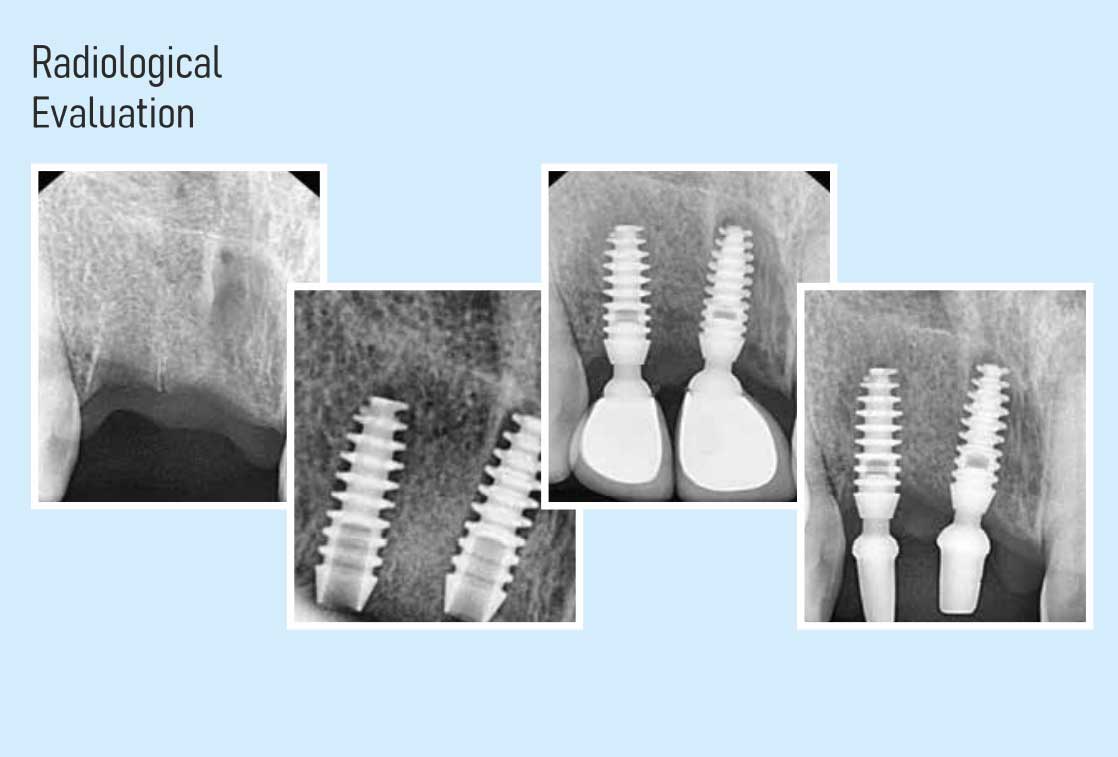

In House Radio Visual Graphics (RVG)

We are using low dose chair side portable radiology with radio visual graphic system which is absolutely vital for accurate planning and placement of impant.it also helps in the accurate evaluation of critical structure, like nerves teeth roots, sinus etc., thereby eliminating any chances of failure occurring due to misdiagnosis.

Our implant centers are equipped with these state-of-the-art machines to ensure a flawless execution of absolutely any type of implant case.